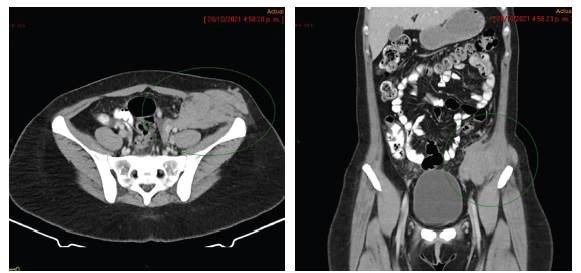

En diciembre de 2021 es valorada en junta de Ginecología Oncológica del INC con imágenes de RM institucionales realizadas una semana antes de la junta las cuales reportan masa que compromete la pared abdominopélvica izquierda a nivel extra e intra pélvica que contacta el borde antimesentérico del colon descendente y signos de carcinomatosis peritoneal (Figuras 1 y 2); la revisión institucional de patología reportó un Tumor de los Cordones Sexuales con Túbulos Anulares (TCSTA) por caracterización histológica e inmunohistoquímica la cual fue positiva para queratina AE1-AE3, inhibina, calretinina, CD56, CD99 (focal) y WT1; la inmunohistoquímica fue negativa para cromogranina y sinaptofisina. El índice KI 67 fue del 10 %. En esta junta se define llevarla a cirugía citorreductora, que es llevada a cabo el 11 de enero de 2022, y se realiza citorreducción vía abierta que incluye histerectomía, salpingooforectomía bilateral, peritonectomía de cúpula diafragmática derecha, peritonectomía parietal derecha flanco y fosa iliaca derecha, peritonectomía pélvica anterior y posterior, resección anterior baja de recto con anastomosis colorrectal, omentectomía supracólica, resección local amplia de pared abdominal de flanco y fosa iliaca izquierda con resección de cicatriz sobrelínea media, resección del ligamento redondo, fulguración y resección de implantes peritoneales en meso del íleon distal, resección del ligamento de treitz. Se calcula Índice de Carcinomatosis Peritoneal (ICP) en 18; este índice tiene un valor mínimo de 0 y máximo de 39, se utiliza para evaluar la cantidad y la distribución de la enfermedad tumoral en el peritoneo 9.